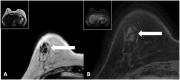

The surgical procedure of AFT and follow-up with imaging modalities including mammography (MG), ultrasound (US), and MRI in patients with a total breast reconstruction with AFT are summarized to illustrate the radiological normal and suspicious findings for malignancy.

Imaging after a total breast reconstruction with AFT appears to be based mostly on benign imaging findings with an overall low biopsy rate. As higher volumes are injected in this technique, the risk for the onset of fat necrosis increases. Imaging findings most often are related to fat necrosis after AFT. On MG, fat necrosis can mostly be seen as oil cysts. The occurrence of a breast seroma after total breast reconstruction with AFT is an unfavourable outcome and may require special treatment. Fat deposition in the pectoral muscle is a previously unknown, but benign entity. Although fat necrosis is a benign entity, it can mimic breast cancer (recurrence).